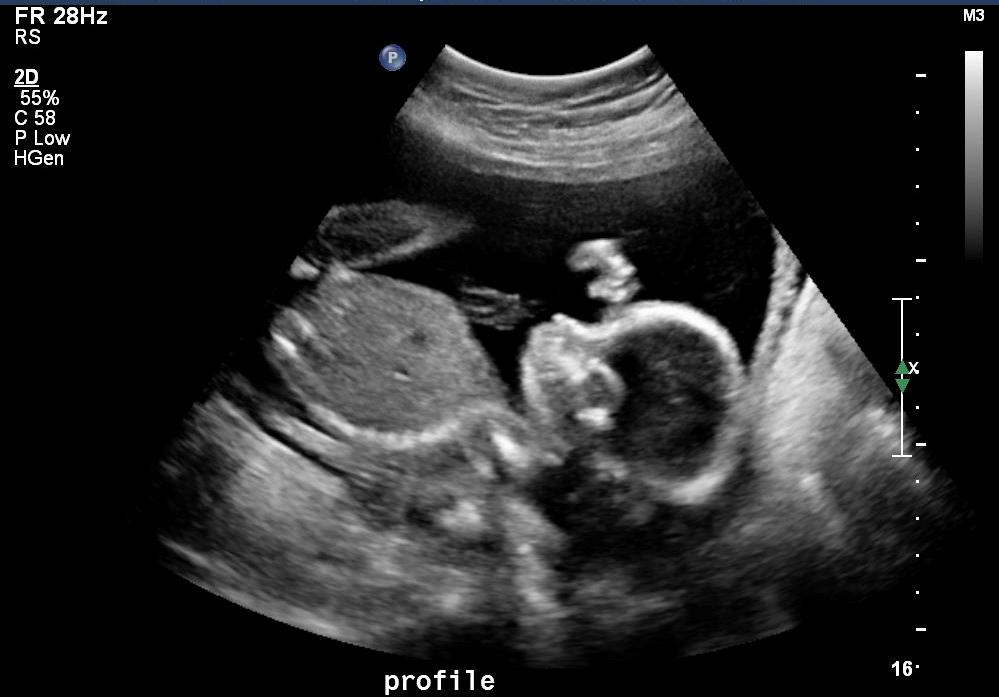

Yup. That’s what the ultrasound gal told your parents and Aunt Maddie. “It’s a boy.” Sometimes it’s tough to tell, she said, because (as with your Uncle Darian) the babies cross their legs. But you, Desmond (or Dezmond, they’re still deciding), were showing off, just like your Uncle Dante did. You’re strong and well-developed and enjoyed posing for the photos, just like your mom did and still does. Last night, your Uncle Dante and I bought you your first onesie . . . it has Jack Skellington on it because ‘The Nightmare Before Christmas’ is your mom’s favorite movie. (Plus, you rather look like him in these photos, huh?) And, oh trust me, we’ve only just begun!